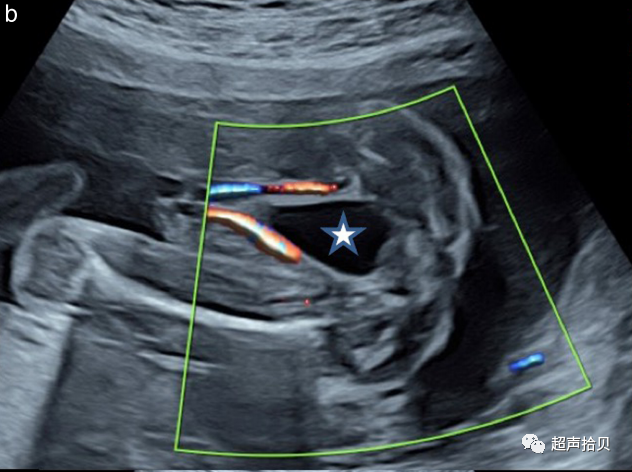

2. 通过直接观察脐带或通过彩色多普勒跟踪胎儿膀胱周围的脐动脉进行诊断;

3. 鼓励使用彩色血流多普勒成像(CDFI),它可以帮助检查胎儿心脏和脐带血管以及确定羊水量。